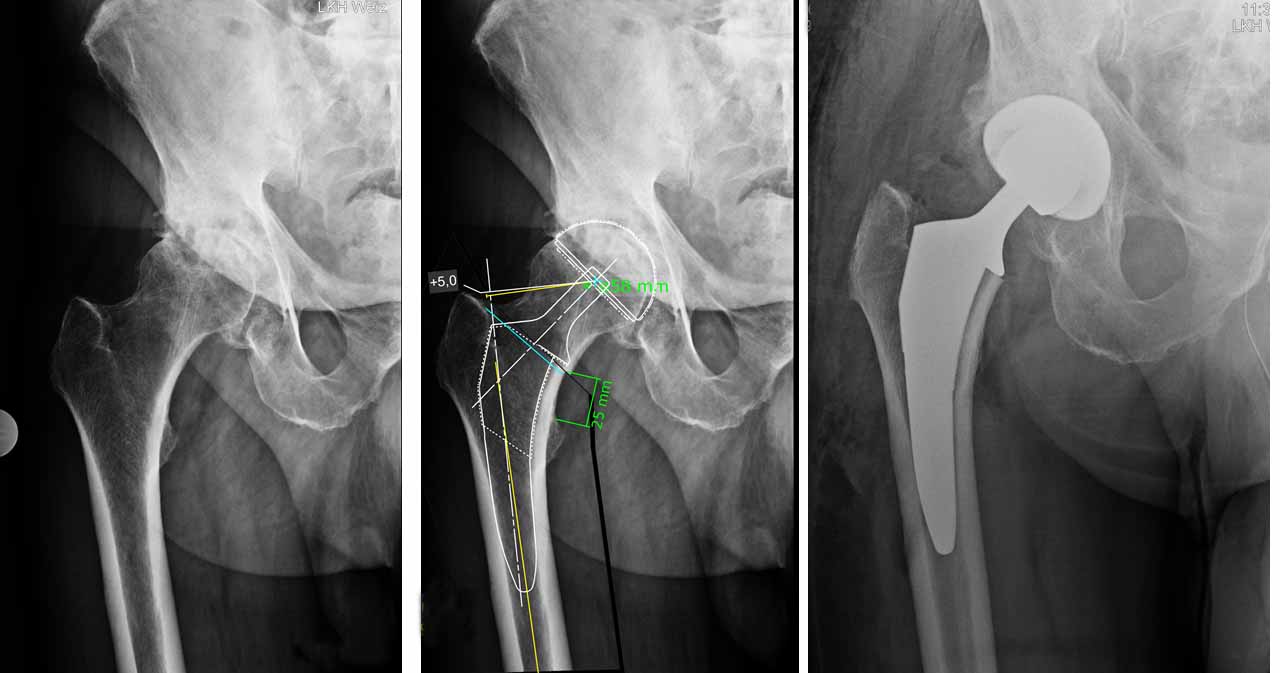

STV. LEITUNG HÜFTCHIRUGIE

LKH-Univ. Klinikum Graz

Als stellvertretender Leiter der Hüftchirurgie an der Universitätsklinik Graz bin ich Ihr direkter Ansprechpartner für operative Eingriffe an der Hüfte. Operation und Nachbetreuung erfolgen persönlich durch mich.